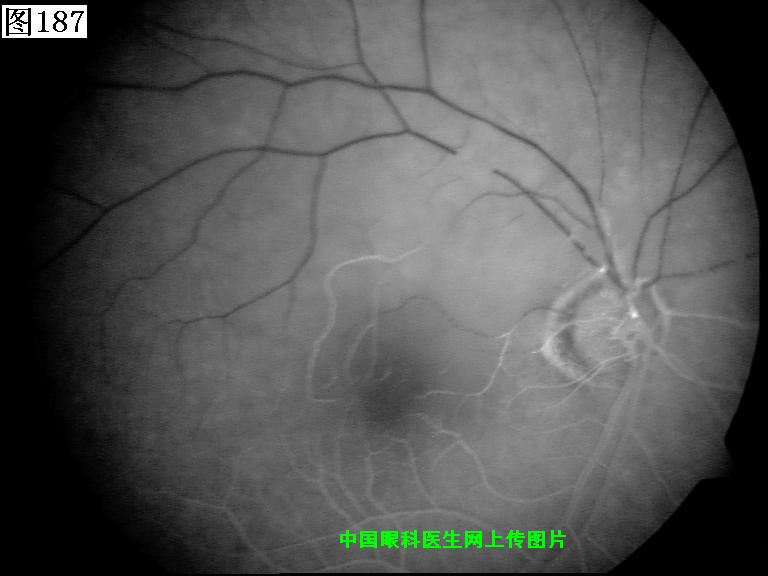

185 186 187 188